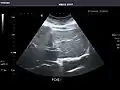

Liver: Diffusely homogeneous and normal in echogenicity. No focal mass or contour nodularity. No intrahepatic biliary ductal dilatation.

Portal Vein: Patent main portal vein.

Gallbladder: No stones, wall thickening, or pericholecystic fluid.

Common Bile Duct: Nondilated measuring 1.3 mm at the level of the porta hepatis.

Pancreas: Visualized portions unremarkable.

Spleen: Normal in size.

Kidneys: Right and left kidneys measure 11.5 cm and 12 cm in length respectively. No hydronephrosis. Small left lower pole kidney cyst.

Ascites: None.

Aorta: Visualized portions normal in caliber, 16 x 15 mm.

IVC: Normal.

IMPRESSION:

Normal abdominal ultrasound.

Liver -